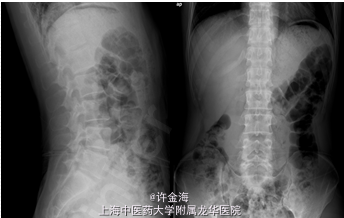

主诉:男,44岁。腰痛伴左下肢麻木、放射痛 一周

检查:L4/S1棘突、左侧棘旁压叩痛(+),左直腿抬高试验15°,加强(+),左4字试验(+),左下肢踇伸、跖屈IV级;浅感觉对称存在,双侧跟膝腱反射(+++),病理征(-)。

腰椎间盘突出症 术前:VAS腰6分,VAS腿8分,JOA12分 行全椎板切除减压,椎间盘摘除,cage融合,植骨内固定